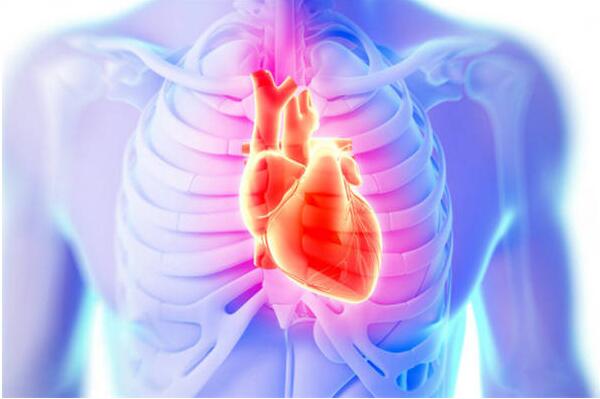

檢查結果顯示,劉先生屬於嚴重的心律失常。而導致這一現象的,是心梗。可是,為什麼劉先生發生心梗的時候,一點痛感都沒有呢?

糖尿病患者最怕遇到的是心梗

這就不得不說到劉先生的糖尿病瞭。原來,糖尿病發展到一定程度,會引起神經病變,導致大腦感受不到心梗所致的疼痛。這就讓患者措施瞭急救的機會。臨床上,很多糖尿病患者因此發生猝死。所以,作為糖尿病人,最悲催的事情就是,明明已經發作心梗瞭,自己卻不知道,連搶救的機會都沒有。可見,糖尿病人必須關註自己的心臟健康。為此,下面這些做法十分必要:1,減少在大冷天出門的機會,避免勞累,減少情緒波動的機會。2,按照規定服用調脂藥物。高血脂是